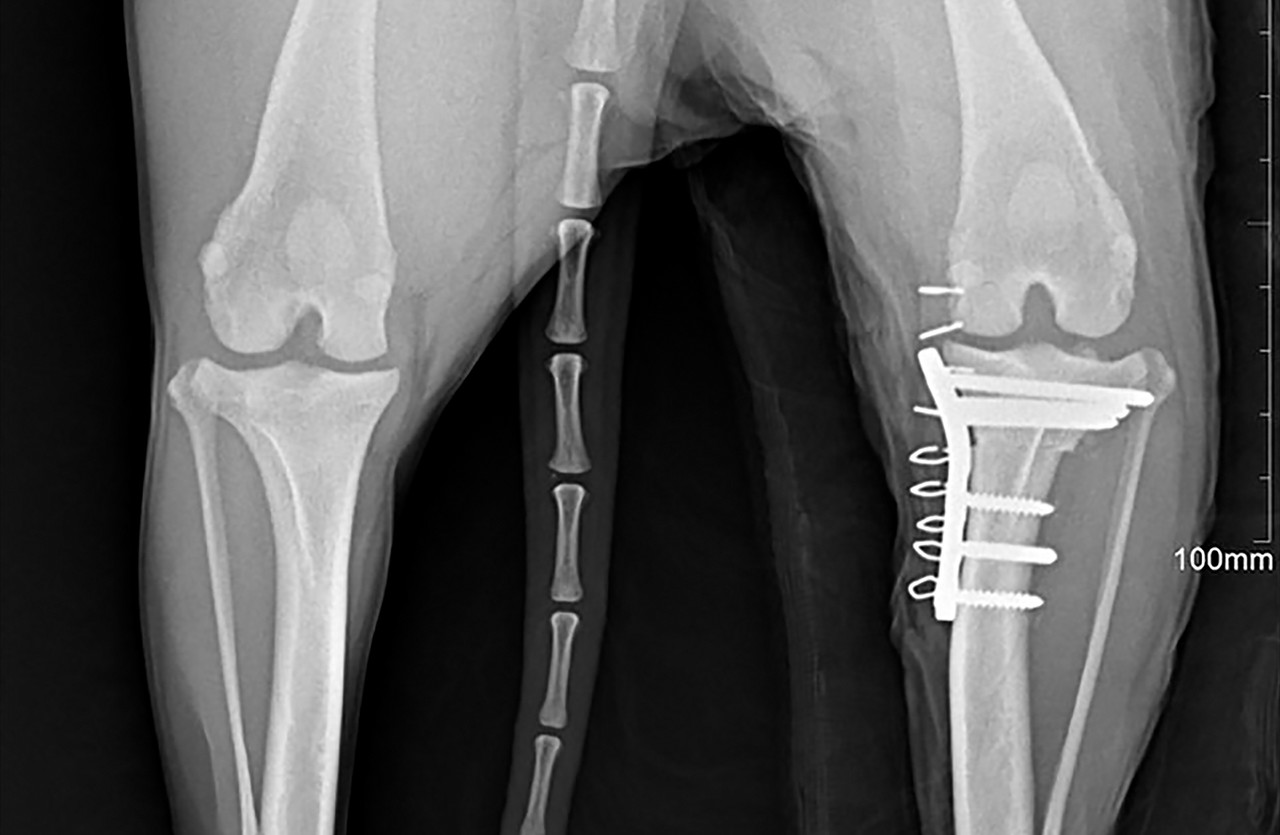

전십자인대 단열

전십자인대는 무릎 관절 내부에 위치하여 허벅지뼈와 정강이뼈를 연결합니다.

개의 전십자인대(CrCL)는 사람의 전방십자인대(ACL)와 해부학적으로 유사합니다.

사람이 경우에는 축구나 럭비같은 운동 중 발생하는 외상성 단열이 주 원인이지만 개는 퇴행성 질환으로 전십자인대 단열이 발생합니다.

TPLO는 절골술을 통해 경사진 경골 고평부의 각도를 완만한 각도로 (3~7도) 바꿔줌으로써 전십자 인대에 의존하지 않고 걸을 수 있도록 하는 수술적 치료입니다.

플레이트 스크류 장비

SYNTHES / biortho / Doiff / Able

골절된 뼈를 고정하기 위해 사용하는 의료용 자재입니다.

체내에 부착되고 체형, 뼈 구조, 골절 형태 등에 따라 맞춤형으로 각각 다른 종류를 사용하게 됩니다.

휴 동물의료센터에서는 안전하고 효과적인 치료를 위해 프리미엄급 플레이트 스크류를 사용하고 있습니다.